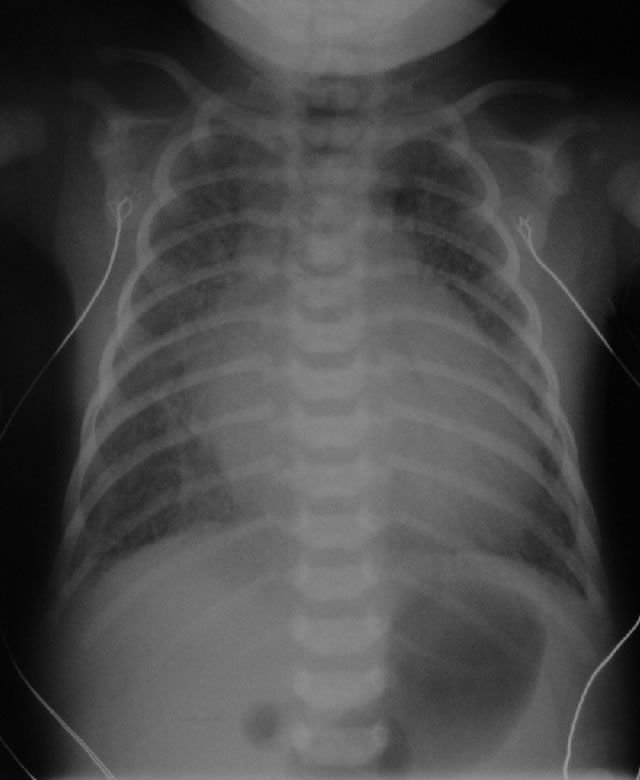

Initial CXR for the case found here:

(CXR source: http://www.adhb.govt.nz/newborn/TeachingResources/Radiology/CXR/HLHS/CXR-HLHS-congested.jpg)